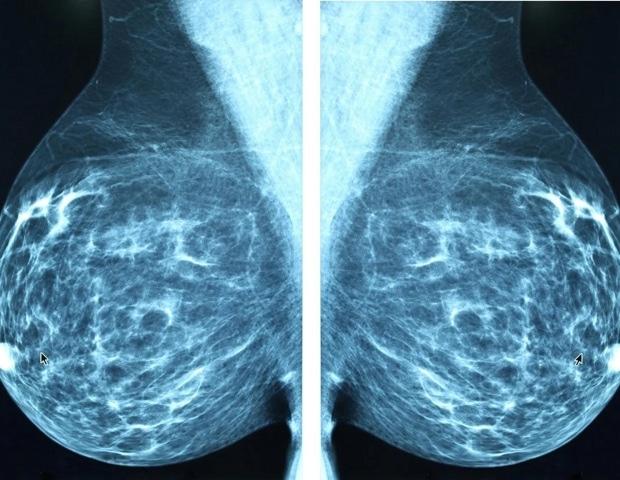

Ο καρκίνος του μαστού παραμένει μια σοβαρή παγκόσμια υγειονομική πρόκληση για τις γυναίκες, με τη διάγνωση σε προχωρημένα στάδια να είναι ένας από τους κύριους παράγοντες που συμβάλλουν στη υψηλή θνησιμότητα. Ιδιαίτερα σε περιοχές με περιορισμένους πόρους, η πρόσβαση σε εξελιγμένα και ακριβά διαγνωστικά εργαλεία είναι περιορισμένη. Έτσι, υπάρχει επείγουσα ανάγκη για οικονομικές, μη επεμβατικές και προσβάσιμες διαγνωστικές στρατηγικές. Αυτή η ανασκόπηση αναδεικνύει τη σημαντική δυναμική των αιματολογικών και βιοχημικών δεικτών ορού ως καίριων εργαλείων για την κάλυψη αυτού του διαγνωστικού κενού, προσφέροντας πληροφορίες για τη διάγνωση, την πρόγνωση και την παρακολούθηση της θεραπείας του καρκίνου του μαστού.